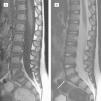

Los datos de seguimiento clínico, recuperados en 11 pacientes, con un tiempo medio de evolución de 2,3 años (rango: 0,5–10), mostraron una evolución favorable, con motilidad normal en todos los niños, y sólo 3 casos de dolor leve-moderado, que no interfería con la escolarización y sí con alguna actividad deportiva. A 17 niños se les realizó control de imagen en un tiempo medio de 14 meses (rango: 1–48); el tiempo de evolución fue igual o superior a 1 año en 9 casos. En todos persistió disminución o desaparición del espacio discal (tablas 3 y 4). Se observó fusión del disco en 3 casos. La RM se empleó como control en 12 niños y mostró siempre mejoría o desaparición de la afectación de partes blandas. Las figuras 3 y 4 muestran la evolución radiológica del paciente expuesto en la figura 2.

RM de seguimiento a los 5 meses. A: Sagital T1. B: Sagital T2. Ausencia de masa de partes blandas perivertebral, canal espinal con diámetro anteroposterior sin impronta paravertebral. Disminución del espacio discal y erosión con irregularidad y esclerosis (baja señal en las dos secuencias) de los cuerpos vertebrales colindantes (flecha).